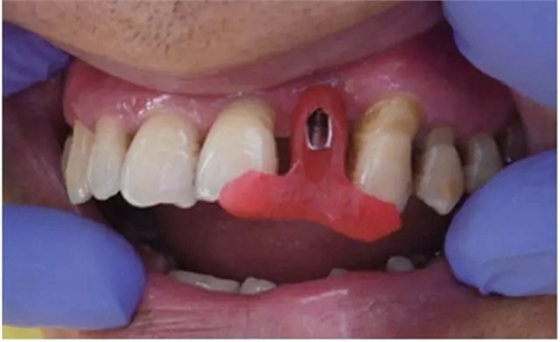

行影像學(xué)檢查(圖2);種植一枚Zuga 3.5*10 mm種植體,扭力≥35 N•cm,旋入愈合基臺(tái)(healing abutment)(圖3、4)。

圖3 22種植術(shù)前后照片